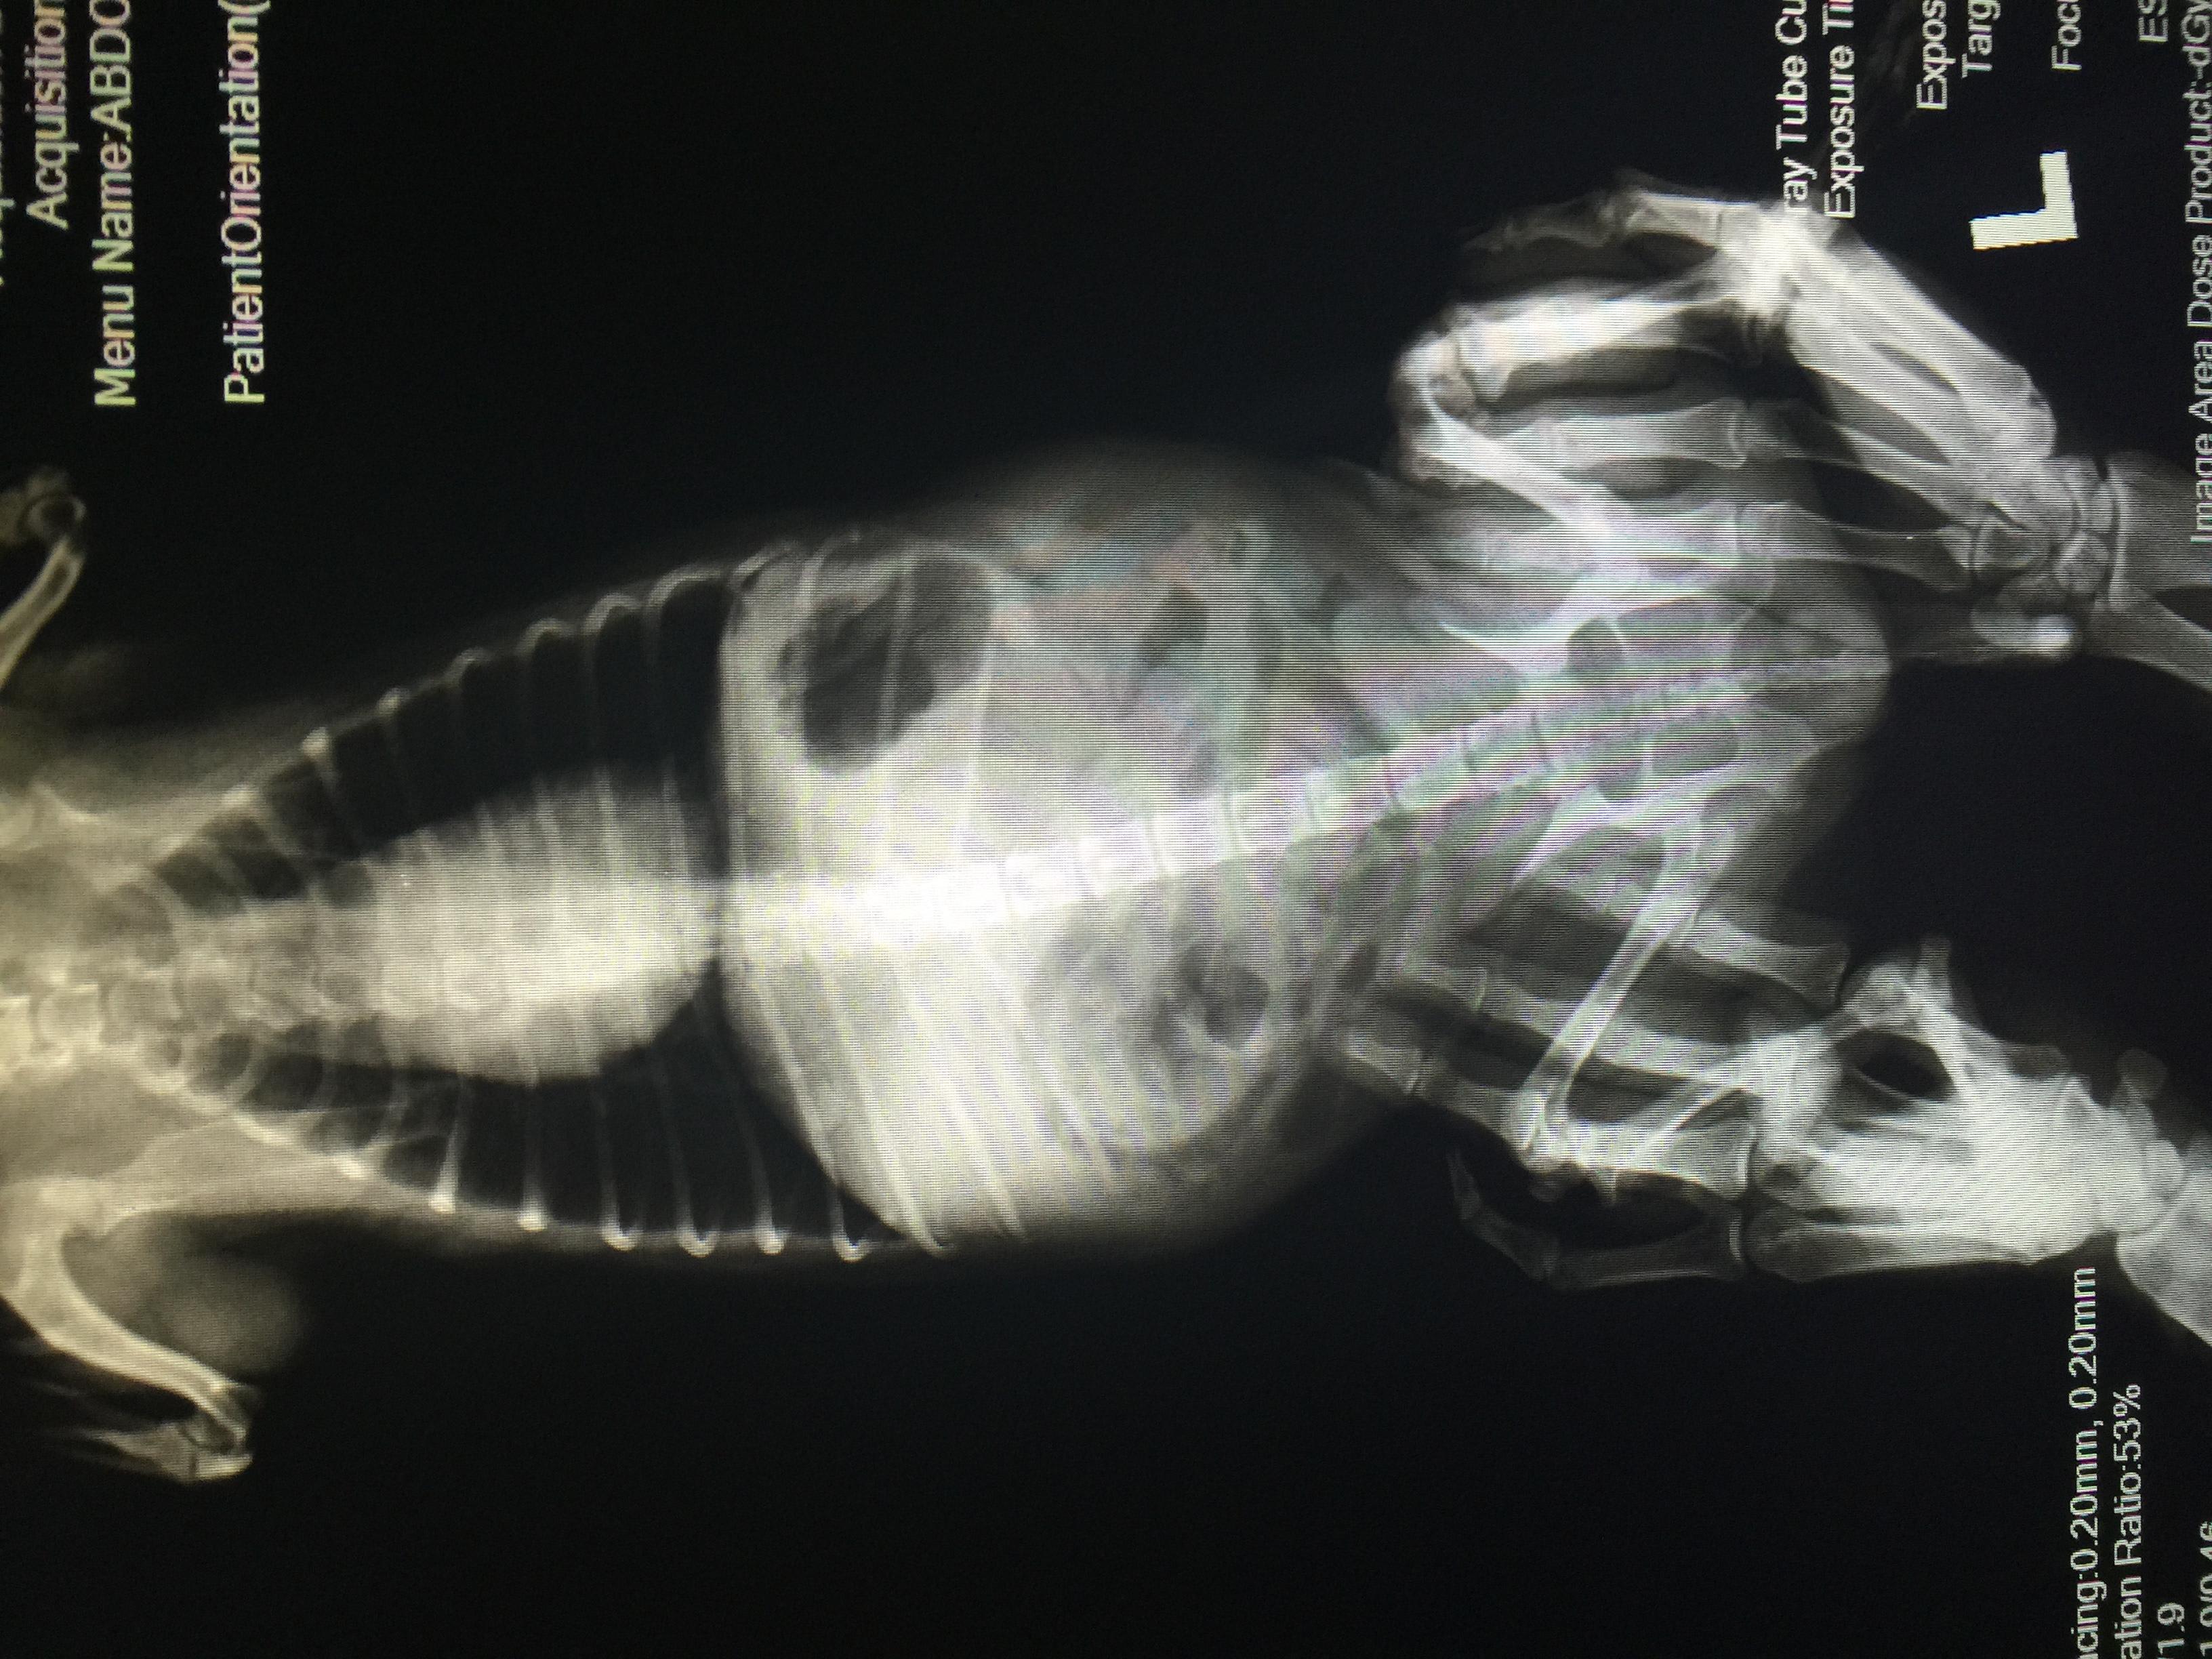

Vet said there's slight inflammation of Maicah's heart, stomach is pushed up -possible pyometra based on her history. See latest xray + old 1/17 sonogram pic attached. Waiting for head vet's feedback based on this am's ultrasound. Maicah is 10-12yo, had 2 CSections- prev. vet did not spay on her last csection, said her uterus was damaged (from prev pregnancies before i adopted her) & there was adhesion so it's risky. How can we get an accurate diagnosis? Is operation still a good option? Thanks!

Unfortunately, the x-rays are not showing up as well here as the originals would, so I'll comment on what I see, but I could easily be missing something. The heart does not appear enlarged, but their are some distended arteries in the x-ray that make me suspicious of heart disease and more specifically heartworm. The abdomen is generally distended and the liver appears somewhat enlarged. This can happen with the heart disease I mentioned or some other condition affecting the liver. I do not see an obvious pyometra on the x-rays or ultrasound (sonogram). I wish I could help you with the other questions, but it's impossible without me knowing the cat's full history, or having the opportunity to examine the cat myself. One thing we can offer on Petco Pet Education Center, formerly Petcoach is a consultation. This is a service that you would have to pay for, but it would allow you to text back-and-forth with one of our experts and send as many pictures as you want. With these consultations, we can help to identify the problems by gaining all the necessary information. Otherwise, you may seek a second opinion from another veterinarian in your area. I hope this is somewhat helpful and everything turns out OK Maicah.